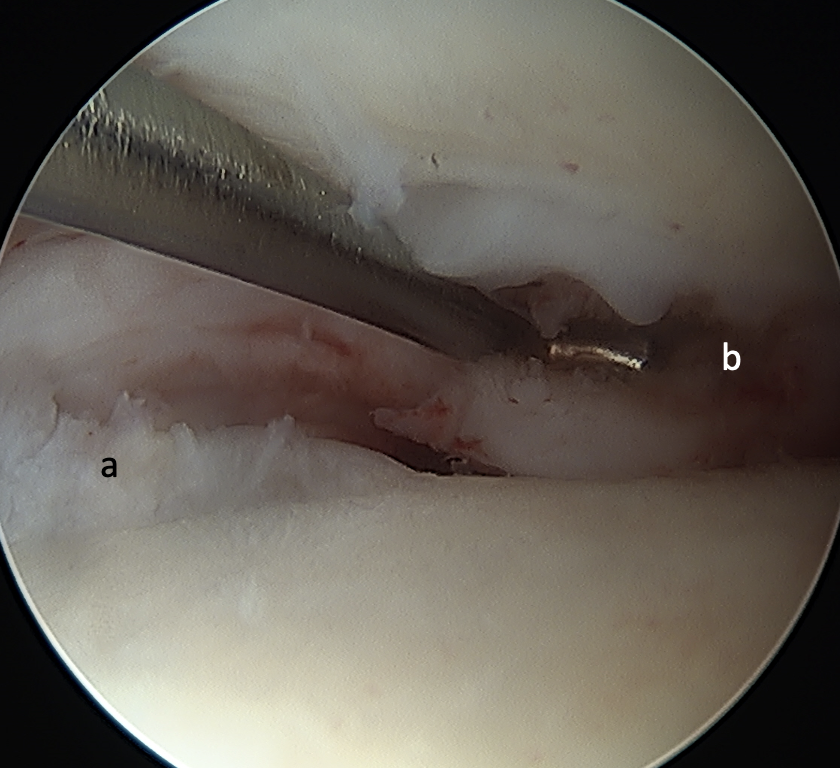

We used the traditional medial and lateral arthroscopy ports for the right ankle. We inserted a NanoScope (Arthrex) 1.9-mm camera into the right ankle joint and maneuvered it around, utilizing a continuous flow of saline at 35 mL radial flow. After adequate visualization of the medial shoulder talus lesion (Figure 3), the lesion was roughly 1.0 cm x 0.5 cm in terms of width and length. We expected a tibial lesion but did not encounter it; nor was it grossly visual intraoperatively. There was anterior tibial spurring.